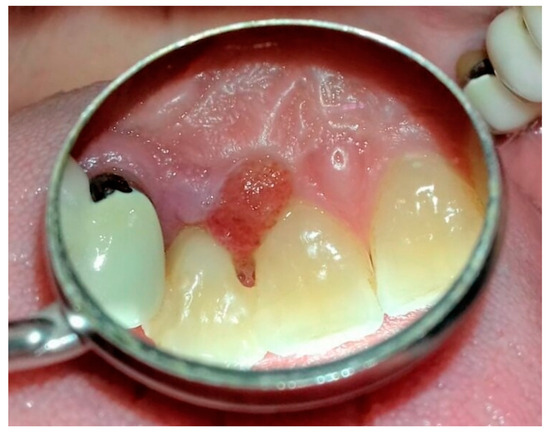

Atypical Gingival Swelling Unrelated to Plaque and Tartar: Diagnostic Difficulty and Conservative Treatment †